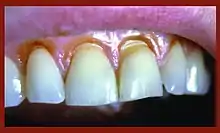

Abfraction is a form of non-carious tooth tissue loss that occurs along the gingival margin.[2] In other words, abfraction is a mechanical loss of tooth structure that is not caused by tooth decay, located along the gum line. There is theoretical evidence to support the concept of abfraction, but little experimental evidence exists.[3]

Tooth tissue is gradually weakened causing tissue loss through fracture and chipping or successively worn away leaving a non-carious lesion on the tooth surface. These lesions occur in both the dentine and enamel of the tooth. These lesions generally occur around the cervical areas of the dentition.[5]

Abfraction lesions will generally occur in the region on the tooth where the greatest tensile stress is located. In statements such as these there is no comment on whether the lesions occur above or below the CEJ. One theory suggests that the abfraction lesions will only form above the CEJ.[6][7][8][9] However, it is assumed that the abfraction lesions will occur anywhere in the cervical areas of affected teeth. It is important to note that studies supporting this configuration of abfraction lesions also state that when there is more than one abnormally large tensile stress on a tooth two or more abfraction lesions can result on the one surface.[3]

When looking at abfraction lesions there are generally three shapes in which they appear, appearing as either wedge, saucer or mixed patterns.[6] Wedge and saucer shaped lesions are the most common, whereas mixed lesions are less frequently identified in the oral cavity.[6] In reference to figure 1, wedge shaped lesions have the sharpest internal line angles and saucer/mixed shaped lesions are either smooth internally, or a variety.

Clinically, people with abfraction lesions can also present with tooth sensitivity in the associated areas. This occurs because as the abfraction lesions appear, dentine/cementum is exposed.[10] The dentine and cementum are less dense than tooth enamel and therefore more susceptible to sensation from thermal/mechanical sources.[10]